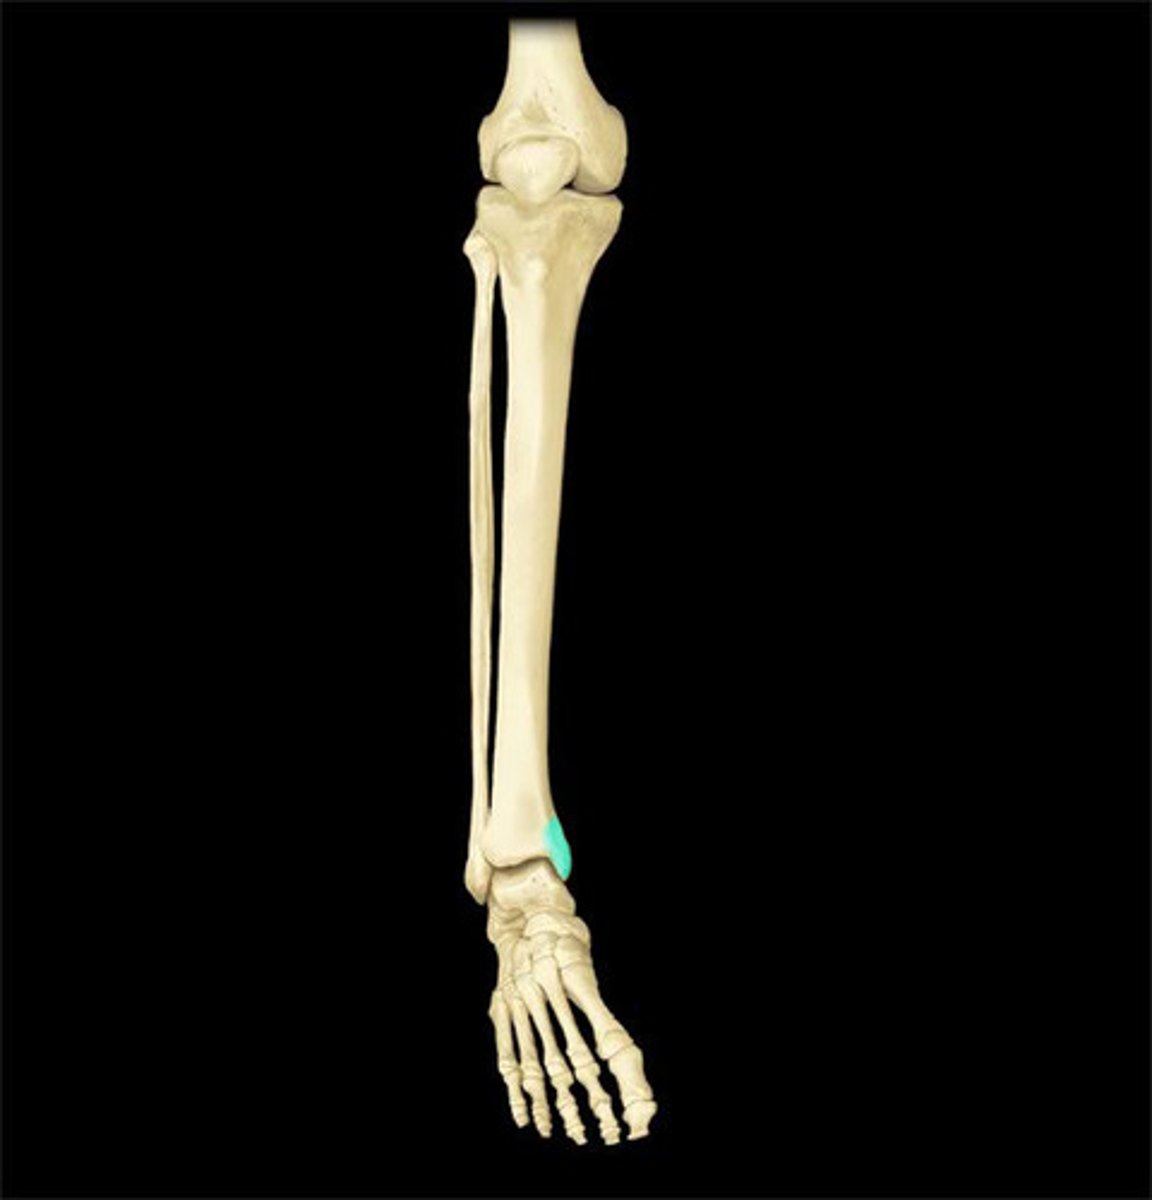

Bones that comprise the ankle (3)

Tibia

Fibula

Talus

A majority of body weight is transferred through the (bone)

What percentage of total body weight is transferred through the tibia?

90% total body weight